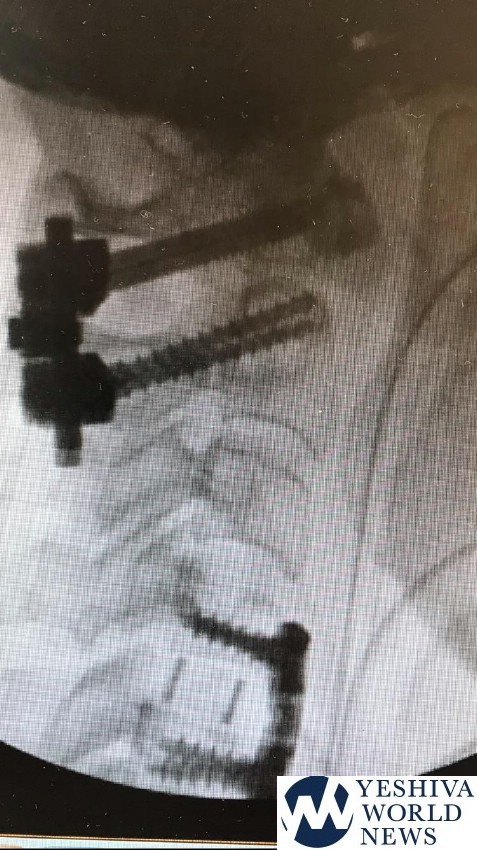

Dr. Amir Sharoni, a leading orthopedic surgeon and specialist in the field of spinal surgery, said that Orlya arrived at the Kaplan emergency room with a cervical collar many hours after a strong fall from a camel in the Sinai. “She arrived with neurological compromise including weak hands, difficulty standing, and severe neck pain. After imaging, she was transferred to the operating room due to a herniation of a vertebral column and a fracture in the first cervical vertebrae. In the operating room, it was first connected to a tensile device to replace the vertebrae, and then we performed two operations; one by one to fix two vertebrae in the neck and spine. The later analysis was a complex back-up approach. She recovered and returned to a stable state and began to walk on her own. “Dr. Sharoni added that Orlya is expected to go a long way in physical rehabilitation and occupational therapy.”

She fell two weeks ago from a camel that went wild during an organized trip to Sinai at the beginning of the immigration to Santa Catarina and underwent two urgent and complex surgeries in the orthopedic unit of Kaplan Medical Center in Rehovot, under the direction of Prof. Yona Kosashvili, to fix a significant fracture in the cervical spine. The two surgeries performed by Dr. Amir Sharoni, a leading spinal column specialist, and Kaplan’s extensive and skilled medical staff, saved her life and prevented possible paralysis. Oralia was transferred to a long and lengthy rehabilitation process in the coming weeks, which will enable her to return to normal routine life in the future.